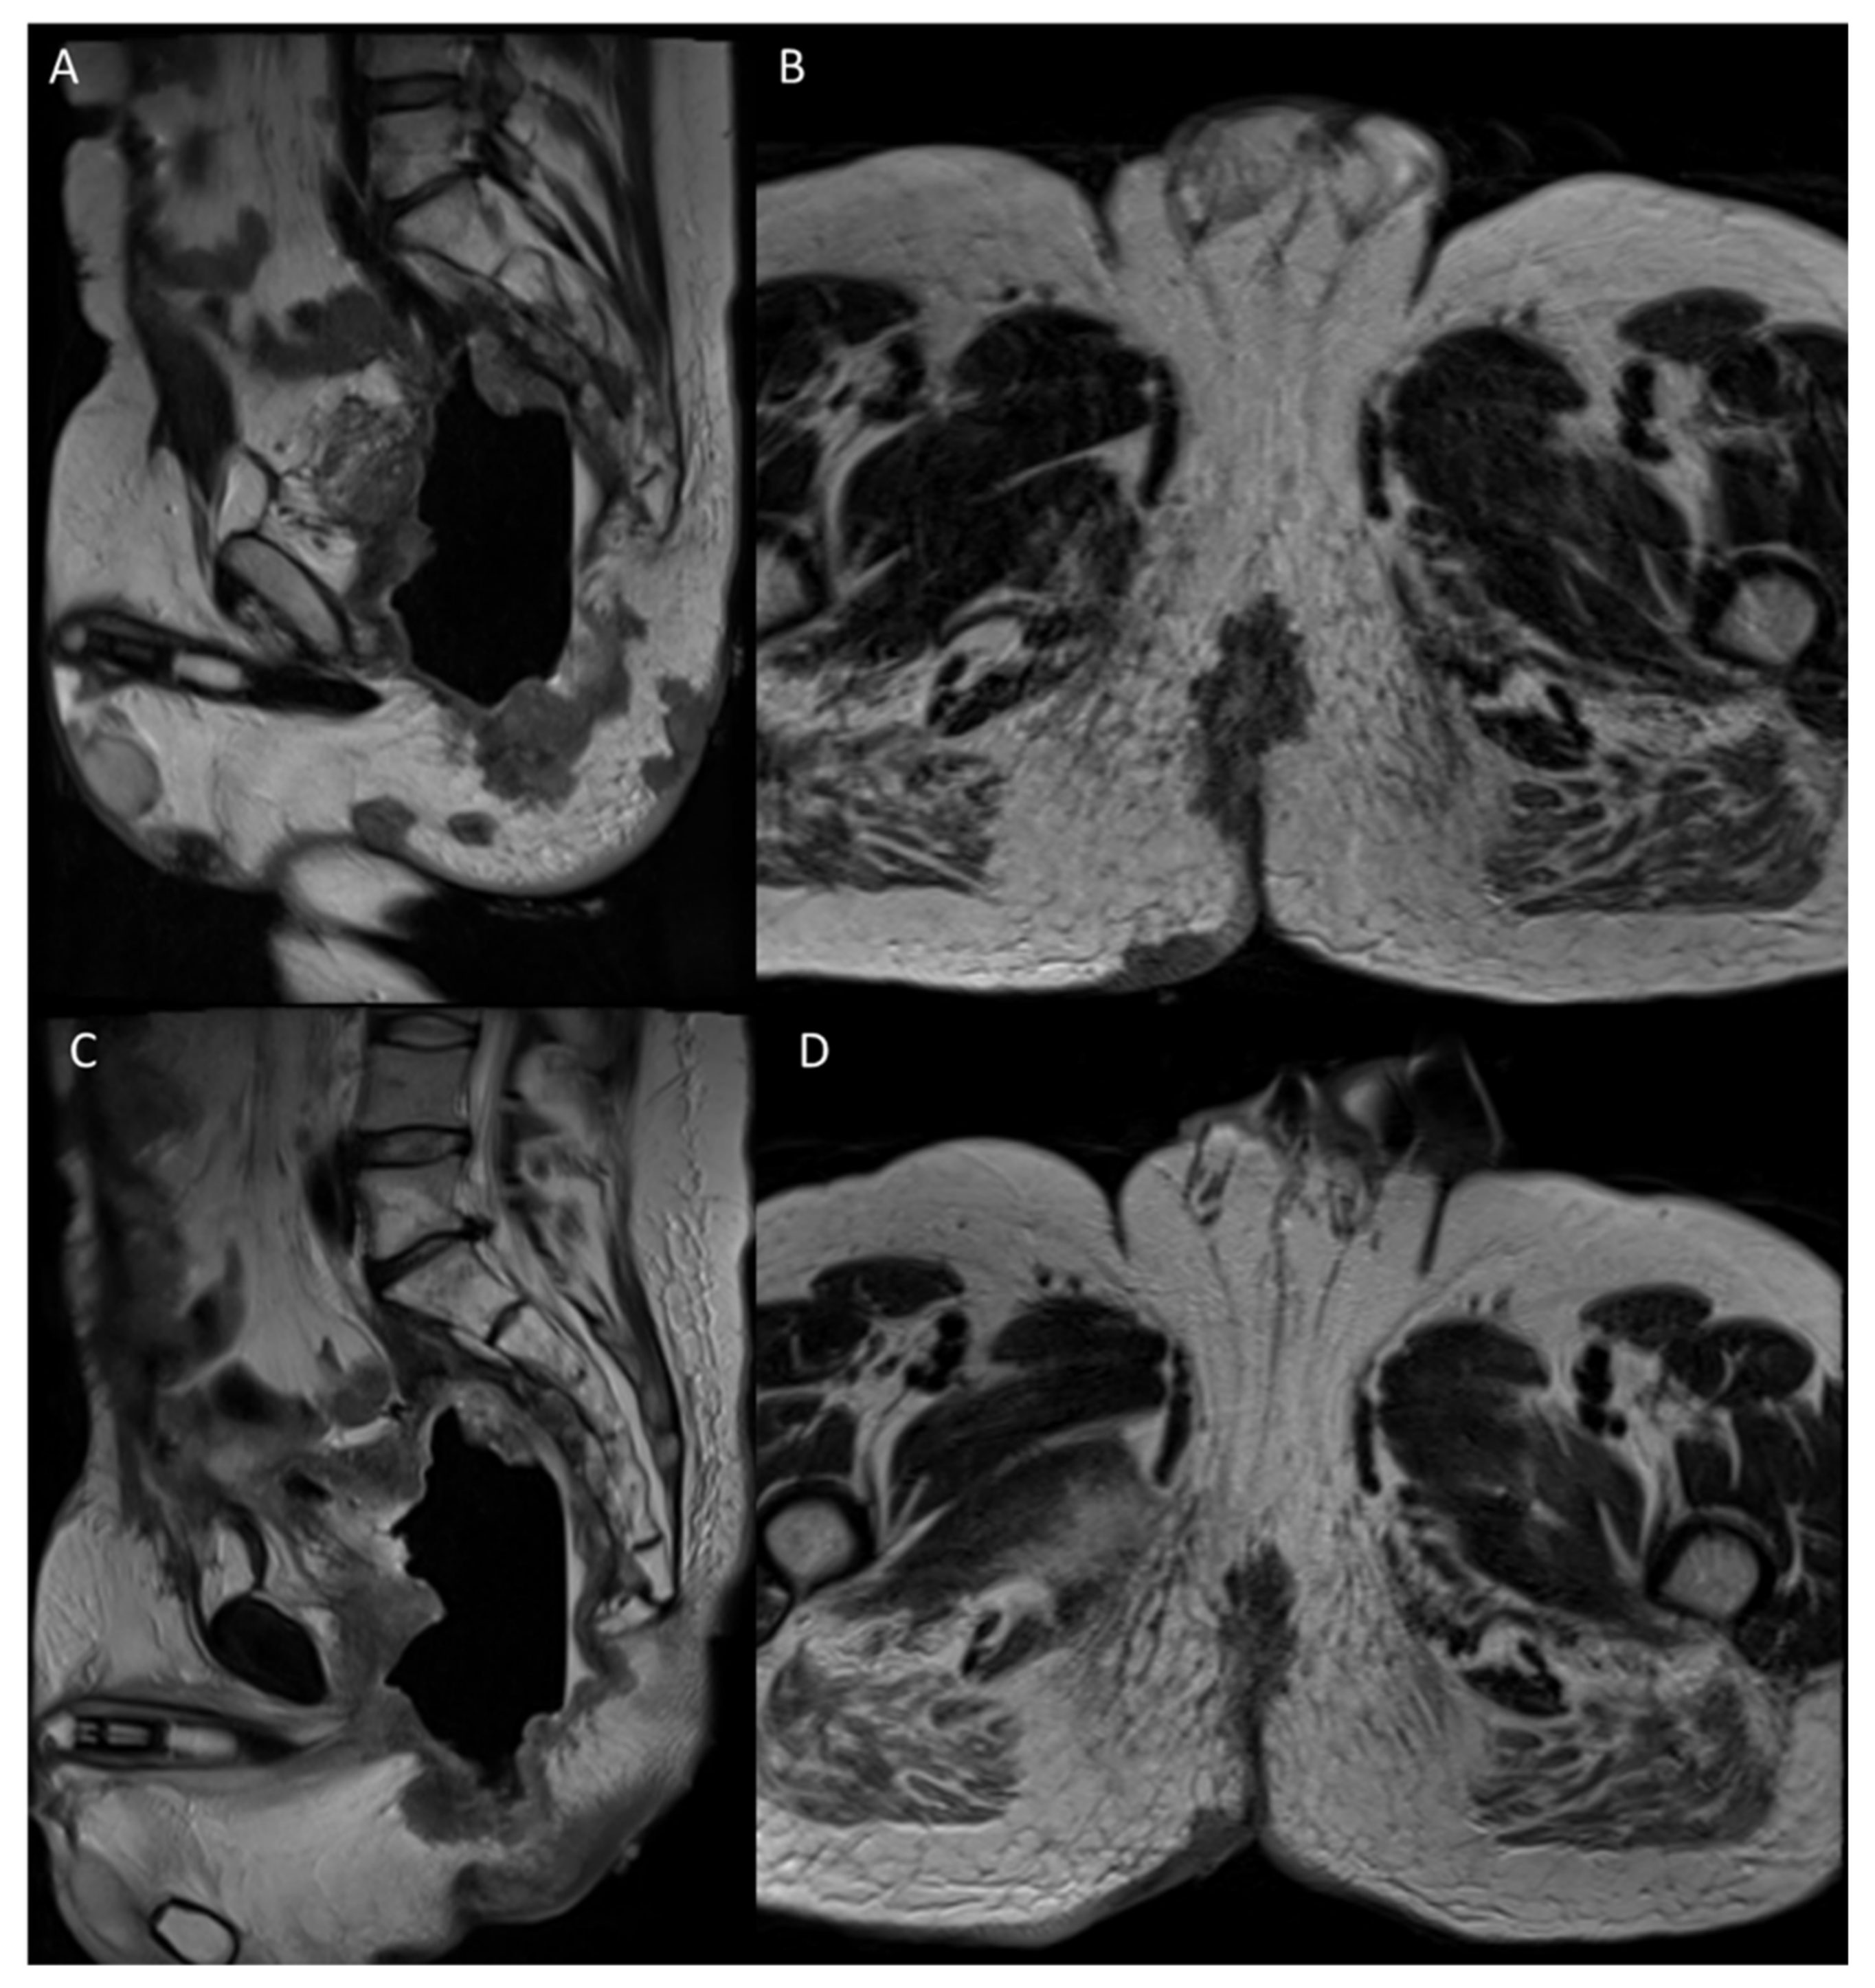

2.4. Third LARC Case Description

| 3 | Male 50 years old with recurrence after long course neoadjuvant therapy and total mesorectal excision (TME) treated with ECT | Variable and fixed geometry electrodes | MRI 6 months after ECT treatment showed no significant morphostructural changes in the lesion that was considered to be stable disease. Patient reported a reduction in pain on the VAS 7 to 4 scale and a reduction in bleeding. |